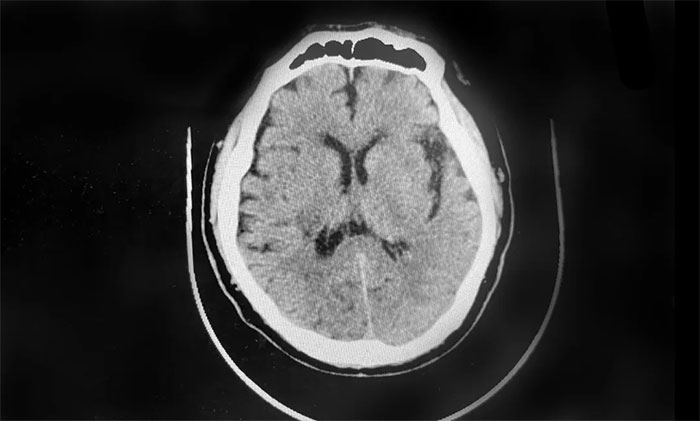

▲ 患者右側(cè)基底節(jié)出血、蛛網(wǎng)膜下腔出血

患者徐老伯(化名)今年73歲。今年2月,其在打乒乓時,突感頭暈伴左側(cè)肢體活動不利,送醫(yī)至就近醫(yī)院。經(jīng)查,患者右側(cè)基底節(jié)出血、蛛網(wǎng)膜下腔出血,給予脫水降顱壓等對癥支持治療。